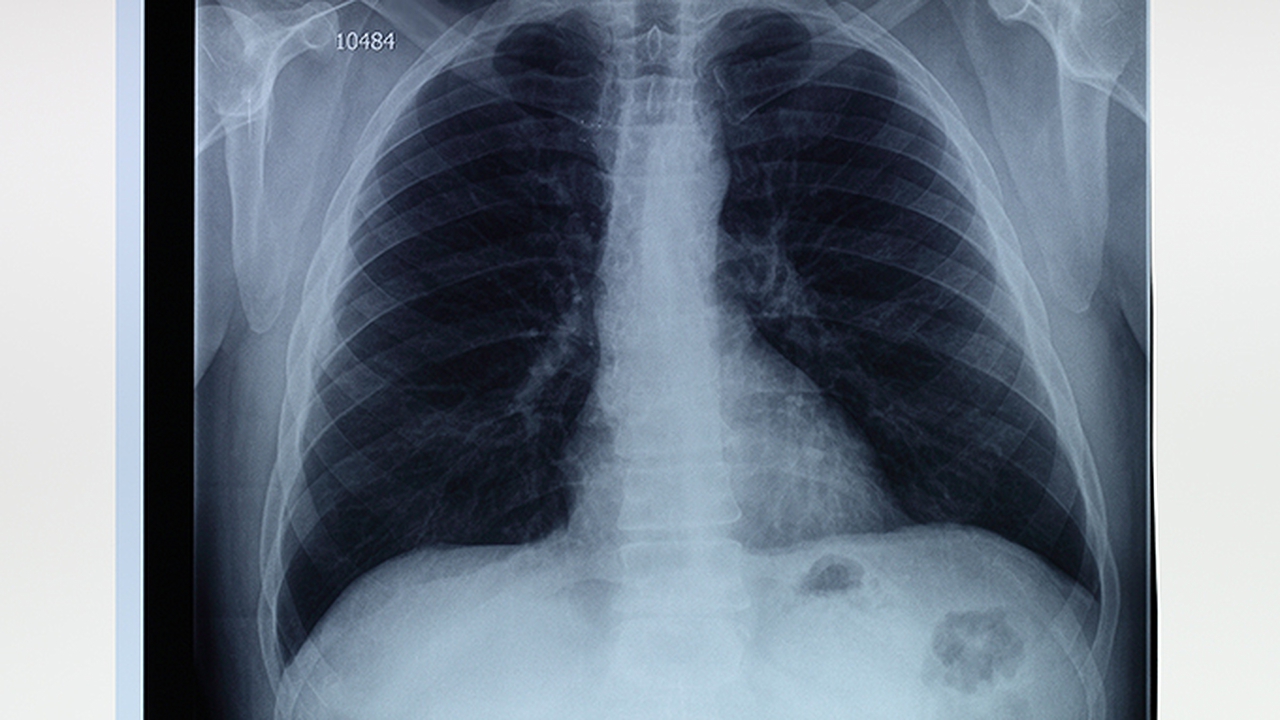

肺气肿是一种慢性阻塞性肺疾病,主要与长期吸烟、空气污染等因素有关。患者会出现呼吸困难、咳嗽等症状,需及时就医治疗。